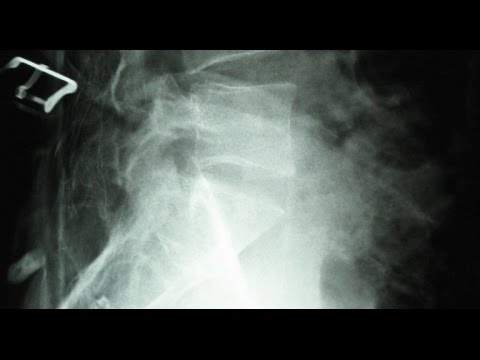

Simulated vertebral endplate fracture by Dynamic Disc Designs

Endplate Fracture by Dynamic Disc Designs Corp.

Disc Herniation and Endplate Fracture by Dynamic Disc Designs Corp.

Video Explanation: What are Vertebral Compression Fractures?